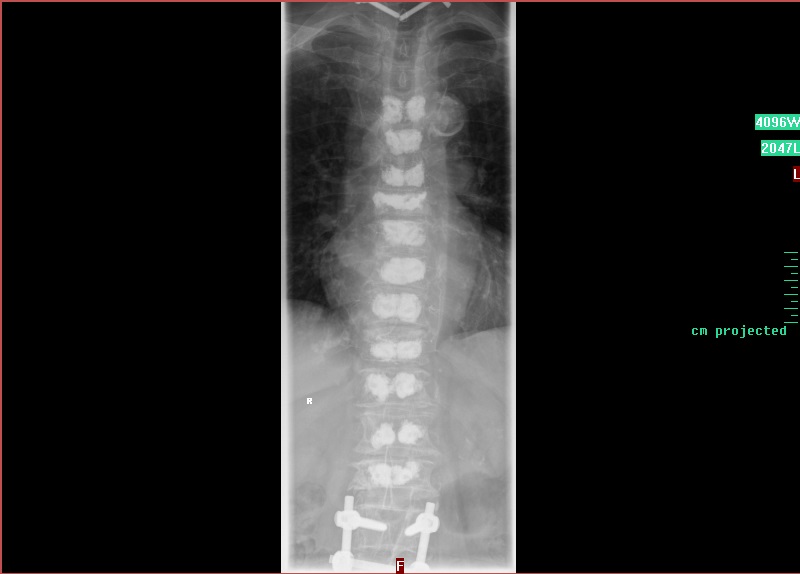

„Das Gute bei der Kyphoplastie ist, dass die Wirbelkörper stabilisiert werden und die Wirbelsäule nicht versteift“, sagt Chefarzt Dr. Richard Delebinski. Die Beweglichkeit bleibt also erhalten. Das Verfahren ist minimal-invasiv möglich, also über kleinste Zugänge – in diesem Fall zur Wirbelsäule. Dort wird über einen Zugang der Knochenzement so gleichmäßig verteilt, dass dadurch der zusammengebrochene Wirbel wieder aufgebaut wird. Gleich am ersten Tag nach der OP ist der Patient wieder mobil.

Damit das nicht passiert, geht Delebinski nun einen Schritt weiter. „Es hätte keinen Zweck gehabt, wieder nur die gebrochenen Wirbel zu operieren“, sagt Delebinski. Stattdessen stabilisiert er nun die komplette Wirbelsäule mit Knochenzement. „Da es sich um eine weit fortgeschrittene Osteoporose-Erkrankung handelt, war die Wahrscheinlichkeit hoch, dass auch die restlichen Wirbel nach und nach brechen.“